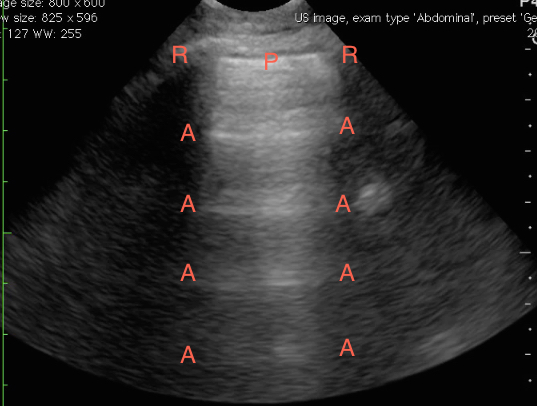

After ruling out a pneumothorax, divide each hemi-thorax into four segments bordered by the posterior axillary line, anterior axillary line, medial clavicular line and the inter-nipple line. Evaluate the lung in each quadrant for lung sliding, A-lines, B-lines, consolidations, and effusions. A-lines are regular horizontal hyperechoic lines that reverberate from the pleural and are indicative of a normal or hyperinflated lung. If all lung segments appear to have lung sliding and A-lines then the patient’s differential is narrowed to that of a patient with a normal or hyperinflated chest x-ray. This may include asthma, COPD, anemia, acidosis, neuromuscular disorders, and pulmonary embolism. If pulmonary embolism is suspected, performing lower extremity deep vein thrombosis (DVT) studies can confirm (but not rule out) the diagnosis. In a prospective, 47 patient study a 2-point compression exam at the femoral and popliteal veins was nearly 100% sensitive and specific for DVT. [14]

Figure 8. Normal lung ultrasound demonstrating A-lines (A) reverberating from the pleura (P) between two ribs (R).